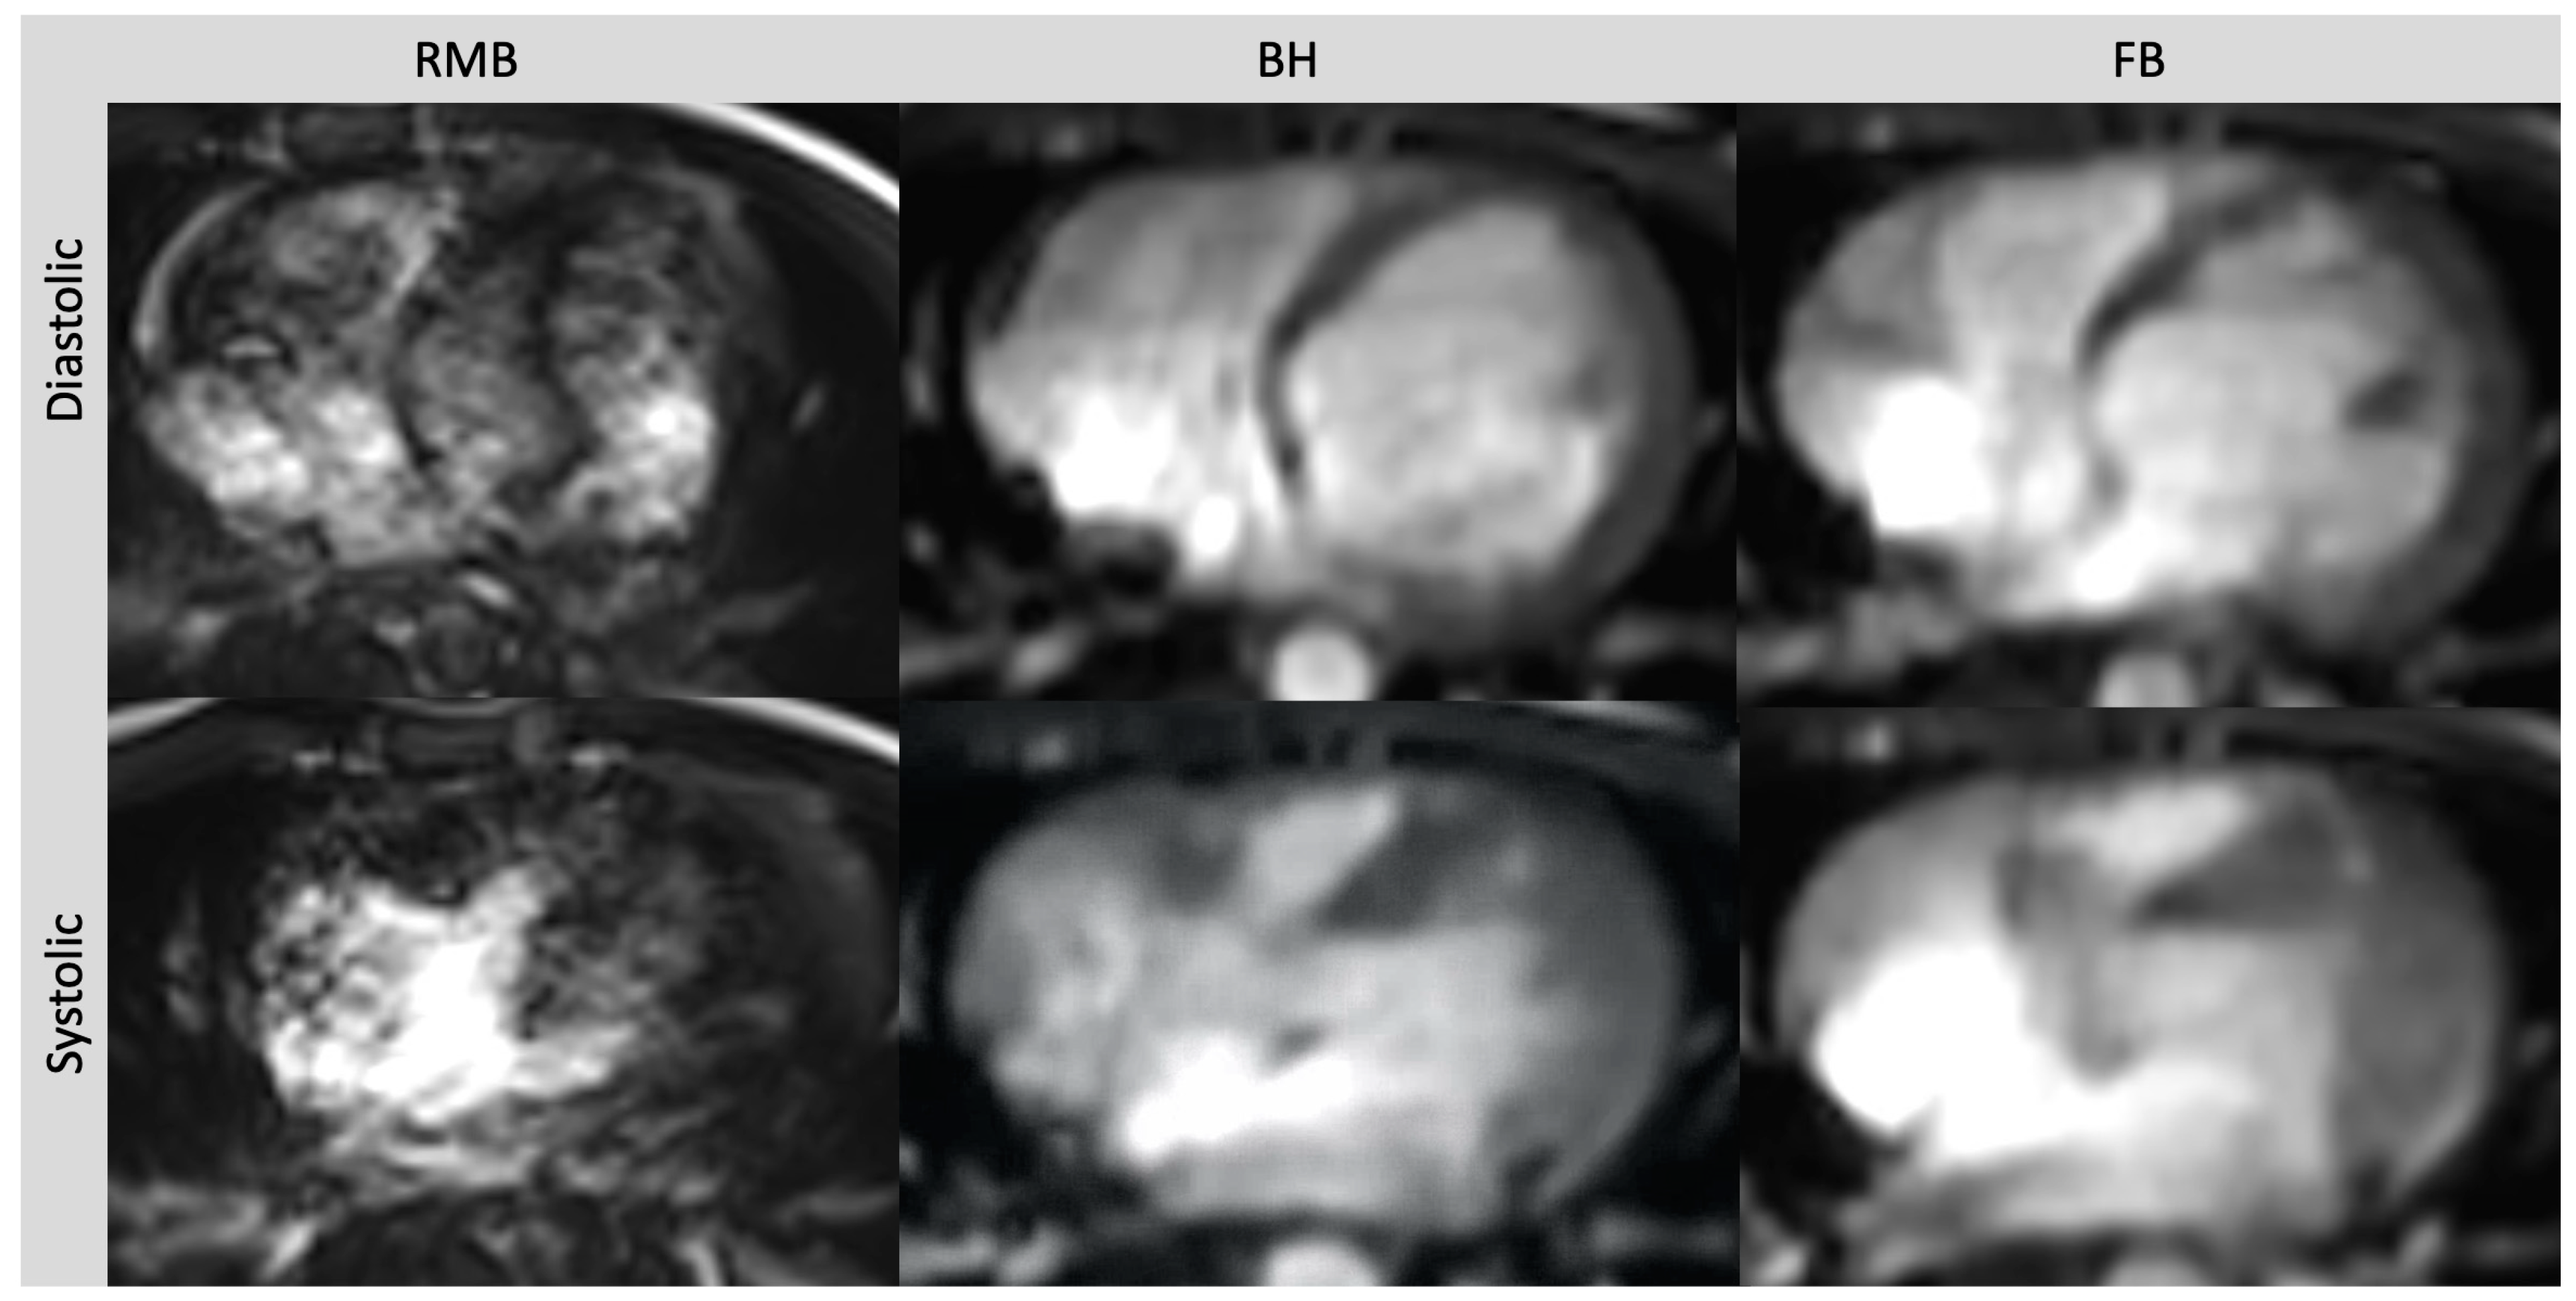

Free-Breathing and Single-Breath Hold Compressed Sensing Real-Time MRI of Right Ventricular Function in Children with Congenital Heart Disease

Treutlein, C.; Zeilinger, M.G.; Dittrich, S.; Roth, J.-P.; Wetzl, M.; Heiss, R.; Wuest, W.; May, M.S.; Uder, M.; Rompel, O. Free-Breathing and Single-Breath Hold Compressed Sensing Real-Time MRI of Right Ventricular Function in Children with Congenital Heart Disease. Diagnostics 2023, 13, 2403. https://doi.org/10.3390/diagnostics13142403